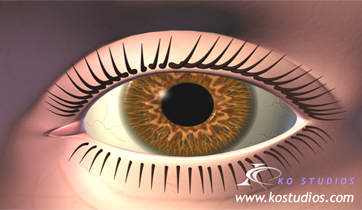

Diabetic Retinopathy

ScienceProd, Paris

Diabetic retinopathy is a condition resulting from micro-vascular retinal changes. Lack of oxygen in the retina stimulates release of VEGF, a factor that causes new blood vessels to grow along the retina and in the vitreous humour. These new blood vessels can destroy the retina by bleeding.